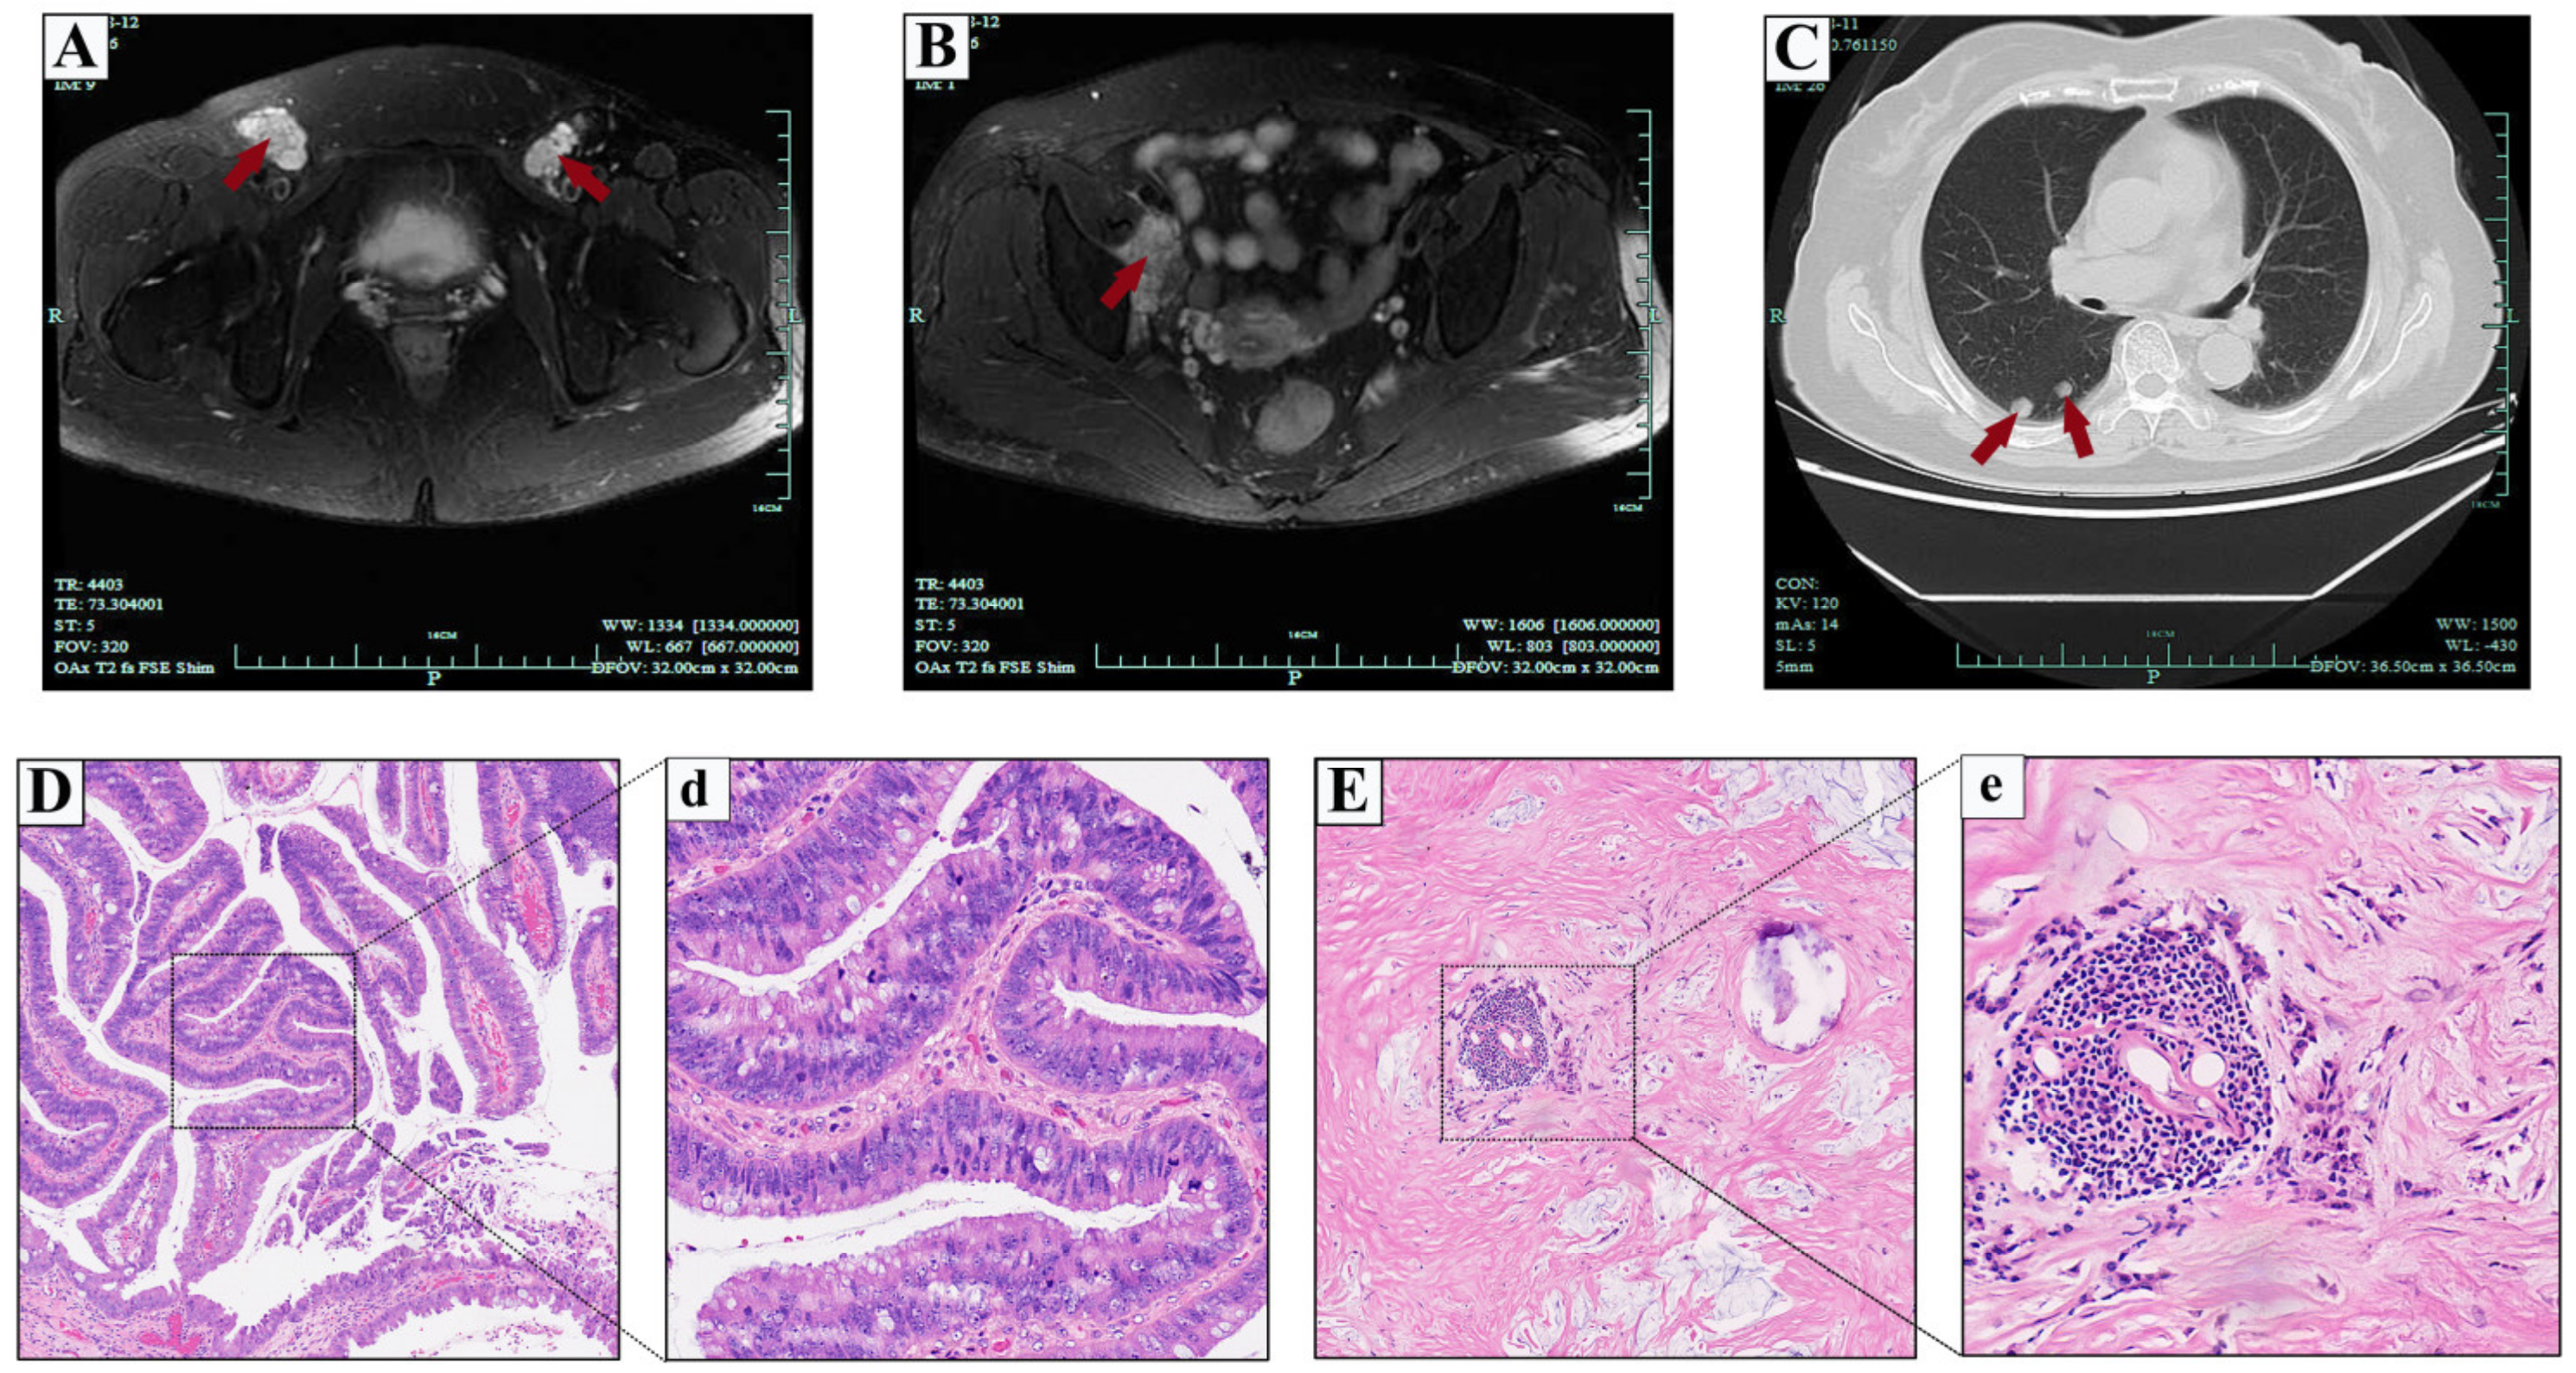

2.1. Case 1

2.2. Case 2